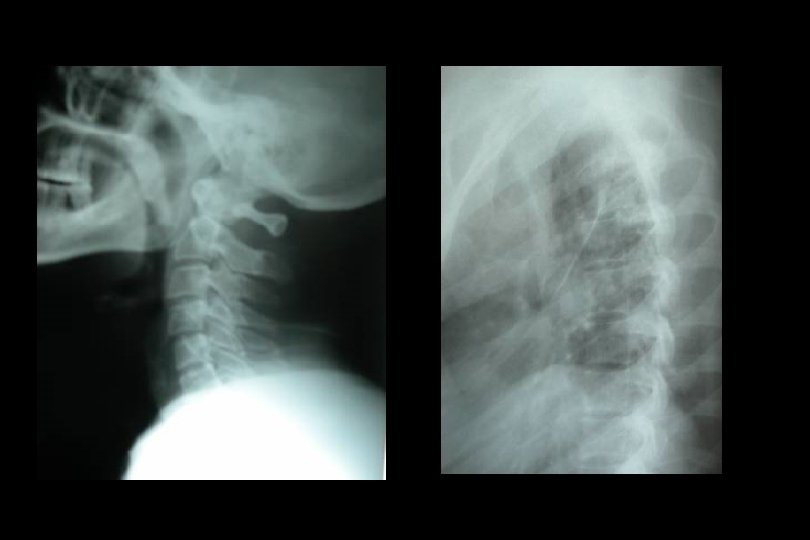

Direkt grafi • • Omurga kanalı ön-arka çapını (13 mm. ) Omurların kontur ve düzlemlerini Kanal içindeki kemik parçacıklarını Lamina, pedikül veya nöral arkların basit veya ortak kırıklarını • Yumuşak doku mesafesinde artmayı – erişkin; C 1=10 mm, C 2 -4=5 -7 mm, C 5 -7=22 mm. – Çocuk; C 1 -4= değişir, C 5 -7=14 mm.

Direkt grafi • • • Torakal ve/veya lomber yaralanmada Pediküllerin iki yanlı simetrisi Omurlarası disk mesafesinin yüksekliği Spinoz çıkıntılarının orta hatta olup olmadığı Omurların konturları Omurga düzlemi